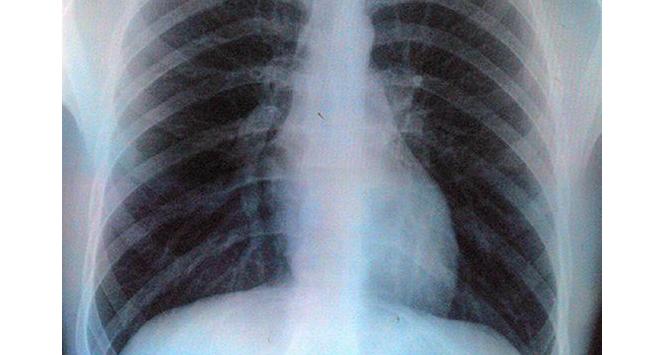

Gruźlica zabija rocznie 1,7 mln ludzi na świecie. Pilnie potrzeba nowych leków. Ale wielkie koncerny nie są nimi zainteresowane. Indie znalazły na to lekarstwo.